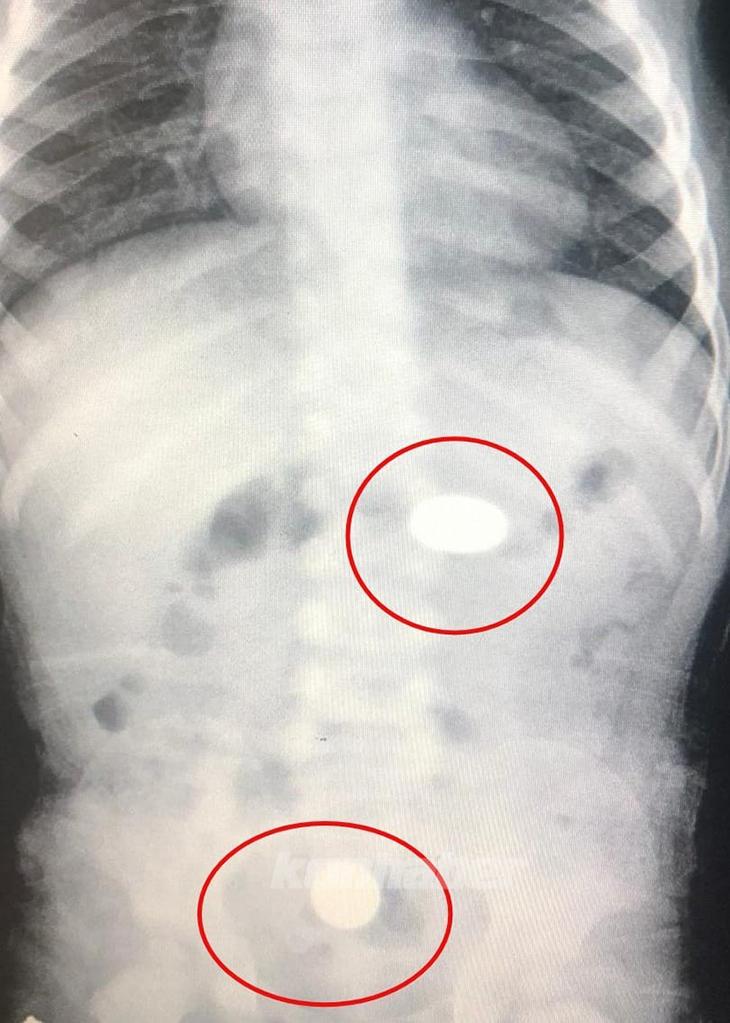

Yapılan tetkiklerde paralardan birinin bebeğin midesinde, diğerinin ise yemek borusunda kaldığı tespit edildi. Sağlık durumunun iyi olduğu belirtilen M.Y., tedaviye alındı.

Yapılan tetkiklerde paralardan birinin bebeğin midesinde, diğerinin ise yemek borusunda kaldığı tespit edildi. Sağlık durumunun iyi olduğu belirtilen M.Y., tedaviye alındı.